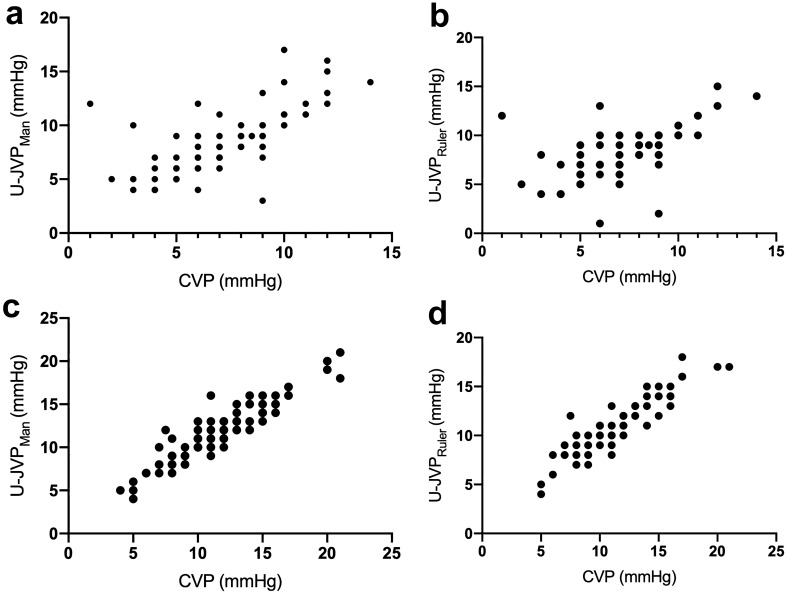

U-JVPMan showed a strong correlation with CVP in ventilated patients (r = 0.72, 95% CI 0.6059–0.7978, p < 0.0001) (Fig. 3a). The U-JVPRuler technique was only able to produce a moderate correlation with CVP, although their relationship remained highly significant (r = 0.63, 95% CI 0.6059–0.7978, p < 0.0001) (Fig. 3b). A total of 15/104 ventilated U-JVPMan readings overestimated the CVP by ≥ 3 mmHg. Only a single case under-read the CVP by a pressure of 6 mmHg. The remaining 14 cases overestimated the CVP, with a mean pressure of 4.7 mmHg higher than the CVP.

Fig. 3.

Scatter plots showing correlation between: a CVP and U-JVPMan in ventilated patients; b CVP and U-JVPRuler in ventilated patients; c CVP and U-JVPMan in non-ventilated patients; d CVP and U-JVPRuler in non-ventilated patients

U-JVPMan and CVP displayed a positive correlation in spontaneously breathing patients (r = 0.93, 95% CI 0.8964–0.9523, p < 0.0001) (Fig. 3c). U-JVPRuler and CVP demonstrated almost as strong a relationship, recording a correlation coefficient of 0.90 (95% CI 0.8526–0.9392, p < 0.0001) (Fig. 3d). Only 6/98 patients measured a difference of ≥ 3 mmHg between the U-JVPMan and CVP (one underestimation and five overestimation). In spontaneously breathing patients, overestimation of CVP by U-CVP occurred in only three patients.